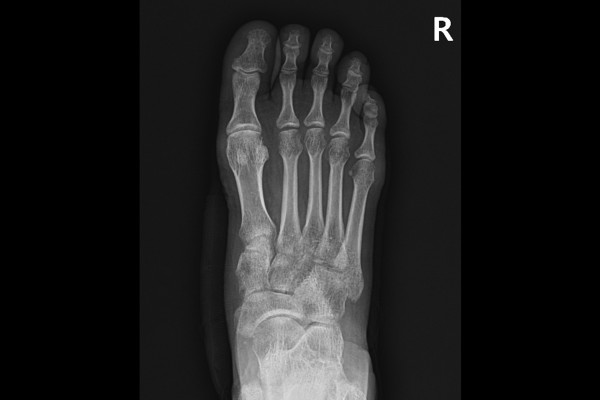

환자분께 현재 발 상태와 수술적 치료의 필요성, 치료 방향을 자세히 설명드렸고, 수술적 치료인 발 중족골 탈구 및 리스프랑 인대 복원술(ORIF c cannul screw for Lisfranc ligament fixation)을 시행하였습니다.

수술은 스크류를 이용하여 인대가 손상되어 벌어진 내측 쐐기골과 제2 중족골 사이를 고정시켜줍니다.

b1d6a7ed823268faf8290a31a2d8a8bb_1765960268_6063.jpg

수술 후 X-RAY 사진을 보시면 인대가 있어야 할 방향으로 스크류가 들어가 잘 고정되어 있음이 확인됩니다.